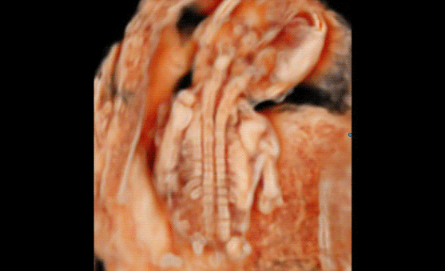

3D/4D成像方面,Hera i 10通過(guò)結(jié)合先進(jìn)的圖像渲染技術(shù),著重加強(qiáng)了邊緣和小結(jié)構(gòu)的可視化能力。